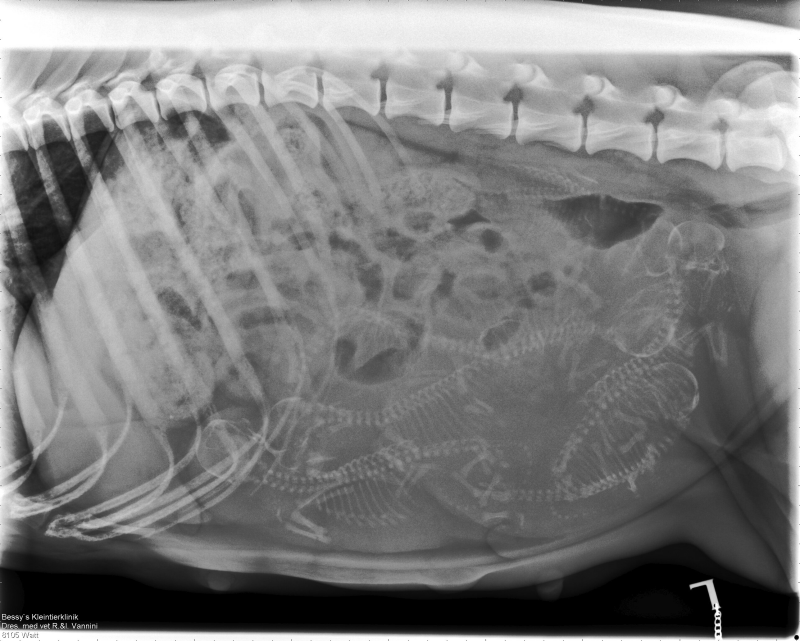

Wir sind bereits in der letzten Woche der Trächtigkeit angekommen und beim durchzählen auf dem Röntgenbild sind wir zum Schluss gekommen, dass Angel 7 Welpen erwartet. Nun hoffen wir, dass sie sich alle weiterhin gut entwickeln und in ca einer Woche gesund zur Welt kommen!